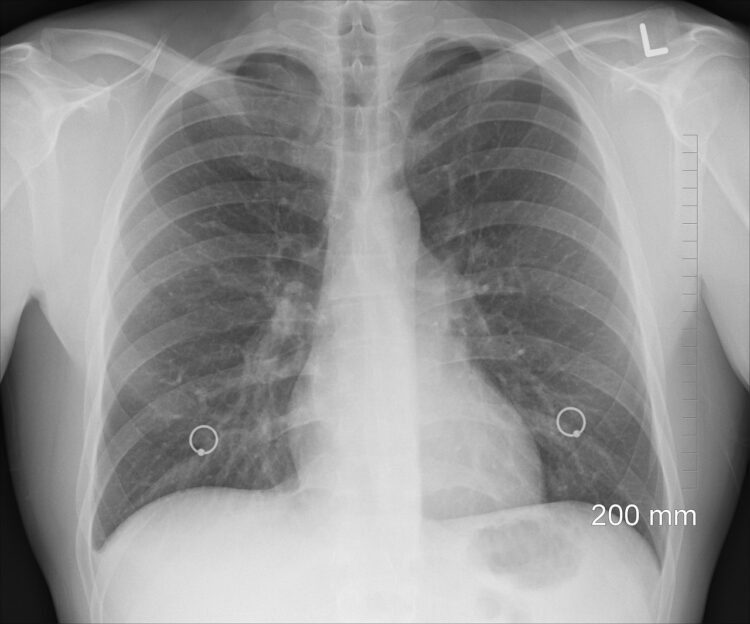

Šance pro české pacienty: Využijte bezplatný screening

Právě včasná a důsledná prevence je u rakoviny plic absolutně klíčová. V České republice je totiž situace ohledně karcinomu plic dlouhodobě závažná. Podle průměrných statistik z let 2019–2023 u nás každý rok tímto onemocněním onemocní přibližně 6 600 osob a přes 5 100 pacientů na něj bohužel každoročně zemře.

Varovným faktem zůstává, že celých 66 % pacientů je diagnostikováno až s pokročilým onemocněním.

Právě proto v Česku funguje bezplatný Program časného záchytu karcinomu plic, určený pro současné i bývalé kuřáky ve věku 55 až 74 let. Jeho cílem je odhalit nádor v nejranějším možném stadiu prostřednictvím moderního nízkodávkového CT vyšetření, které je zcela bezbolestné.